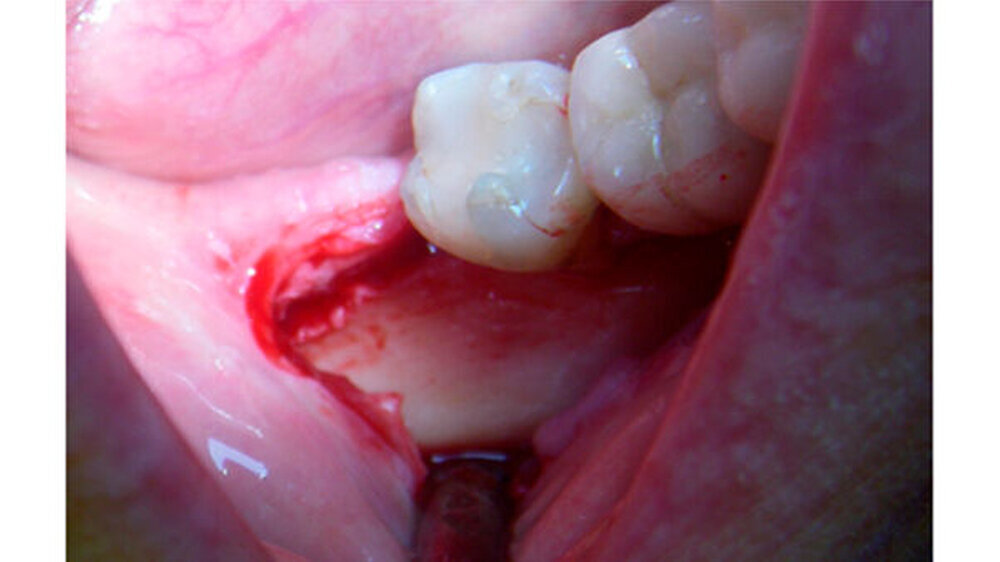

Der Zahn 47 reagierte positiv auf den Vitalitäts-/ Sensibilitätstest. Eine dreidimensionale Bildgebung musste von der Patientin aus wirtschaftlichen Gründen abgelehnt werden. Die Verdachtsdiagnose: ein Osteom oder ein Zementom. Zur explorativen Probeexzision wurde nach minimalinvasiver Schnittführung ein Knochendeckel präpariert, was eine berührungslose Darstellung der knöchernen Veränderung erlaubte. Weil die Veränderung sehr hart und spröde war, konnte sie nicht in toto entfernt werden.

Klinisch zeigte sich, dass die knöcherne Veränderung nicht mit Blutgefäßen durchsetzt war. Erst nach vollständiger Entfernung konnte in der Defekttiefe aus der angrenzenden lingualen Spongiosa eine Blutung provoziert werden. Histologisch wurde ein Osteom aus kompaktem, regressiv verändertem Lamellenknochen mit überwiegend leeren Osteozytenlakunen sowie sehr vereinzelt unreifes Osteoid mit aktivierter Bindegewebszone nachgewiesen.